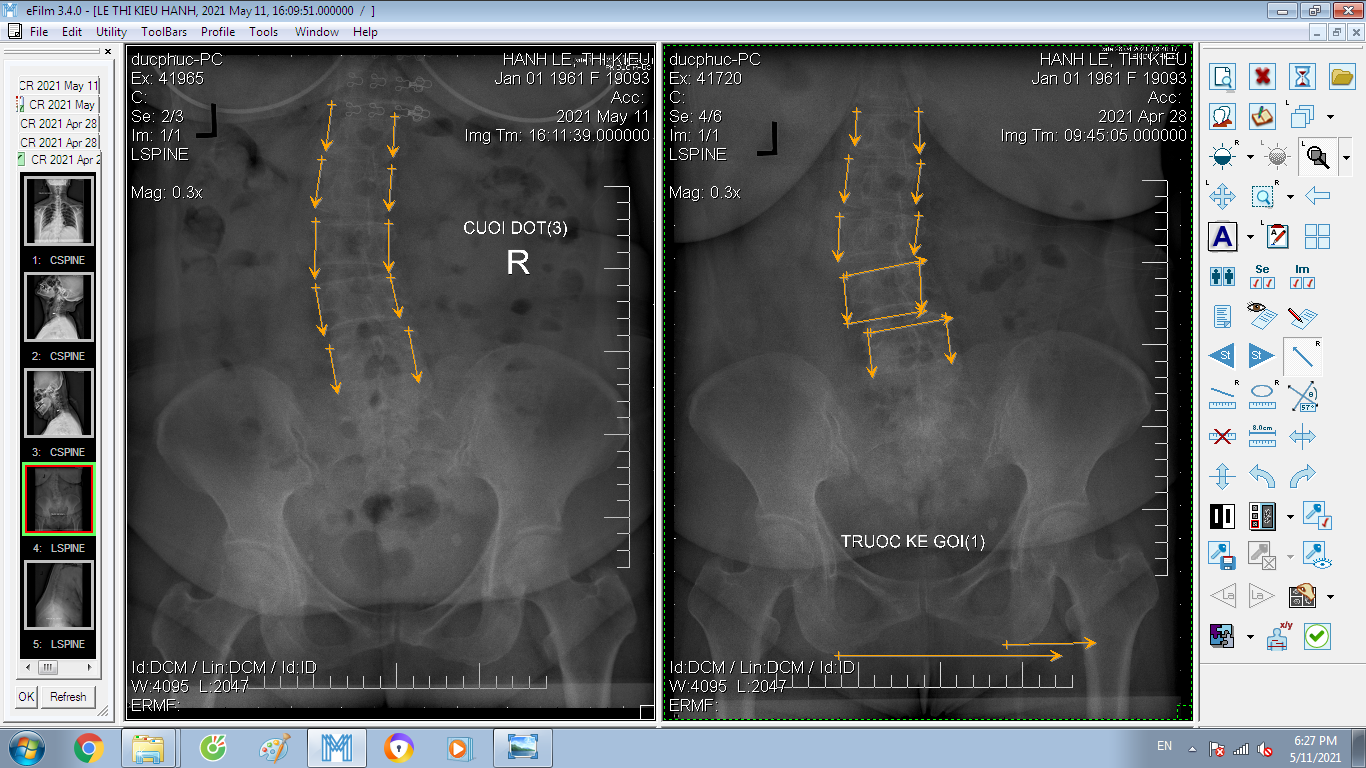

DOCTORLOAN đã thành công trong điều chỉnh xương khớp về đúng vị trí trong thời gian ngắn